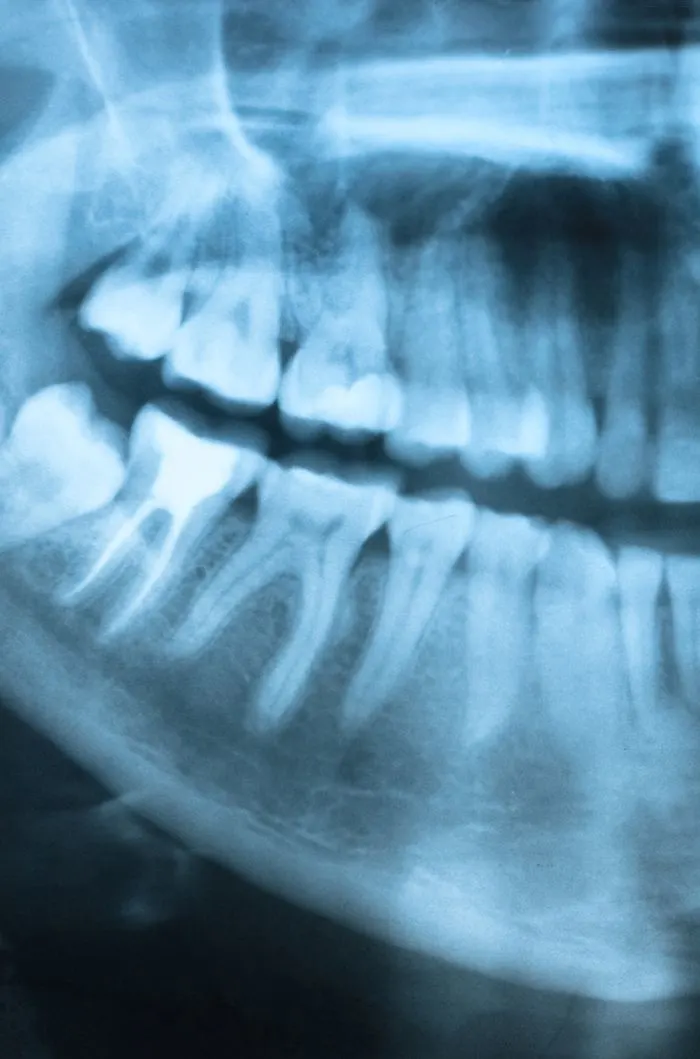

During your consultation, we’ll take digital x-rays to assess the condition of your tooth and the surrounding bone. We’ll explain whether extraction is truly necessary and walk you through any alternatives. If you’re moving forward, we’ll review the number of teeth to be removed, aftercare expectations, and any follow-up recommendations for tooth replacement. We’ll answer every question you have so you feel fully informed and know what to expect.